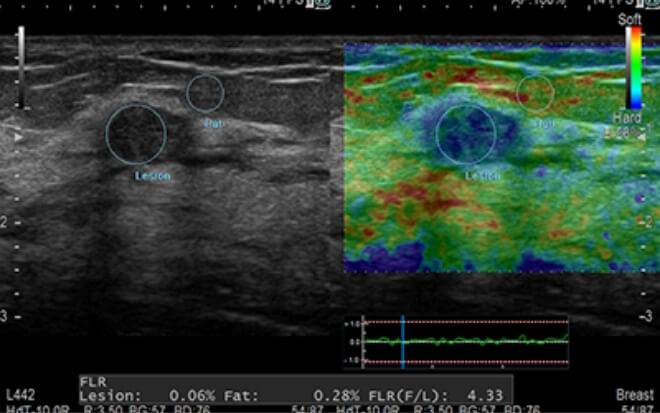

超音波検査

体に負担をかけず、臓器や血流の状態をリアルタイムで観察します。

乳房

¥13,200(税込)

乳がん検査

乳房の状態をより精密に確認し、乳がんの早期発見に有用な検査です。

乳房自動超音波(ABUS)

乳房に超音波機器をあて、内部の状態や石灰化の有無などを確認する検査です。乳房を圧迫しないため、痛みを感じにくいとされている、高精度な超音波検査です。

*痛みの感じ方には個人差があります